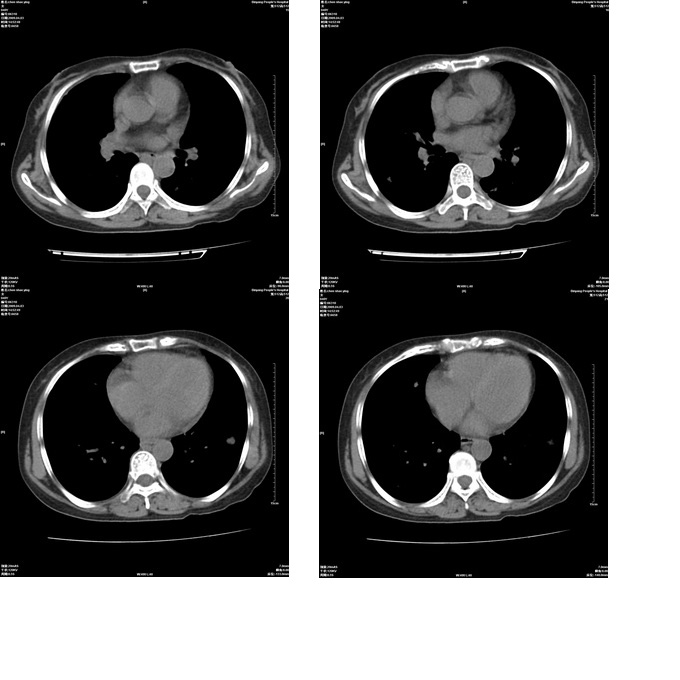

患者,女,48岁,发热伴陈发性咳嗽5天,偶尔痰中带血。体温约38°~40°;白细胞明显减低0.85x10的9次方/升。入院后抗炎、抗痨一周复查病灶明显进展。

右上肺后段实变影,内见支气管气象,肺门未见软组织肿块,气管前方有肿大淋巴结。左下肺见多个类圆形结节影。考虑:1.右上肺后段大叶性肺炎,需进一步检查病原体种类,应多询问病史,条件许可考虑做纤支镜检查2.左下肺结节影性质待定

考虑右上肺后段大叶性肺炎不除外结核,伴双肺结节播散灶,希定期复查。

问题是抗炎治疗一个星期后病灶进展。

右肺于酪性肺炎并左肺播散。

考虑干酪性肺炎

考虑两肺继发性肺结核(右肺上叶干酪性肺炎?)。

考虑两肺继发性肺结核(右肺上叶干酪性肺炎)。

右肺干酪性肺炎并左肺播散。